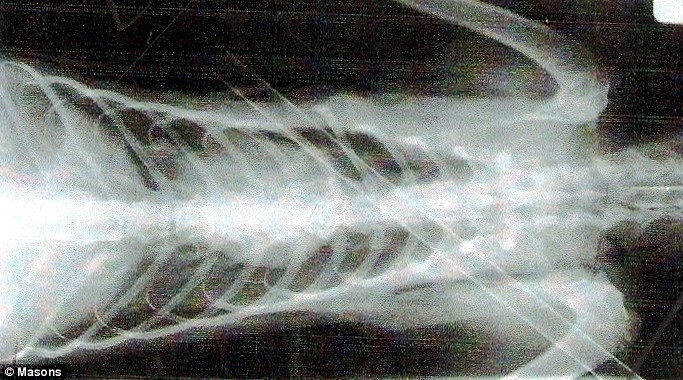

11-месячный кот более недели проходил пронзенный насквозь арбалетной стрелой. Только через восемь дней он смог добраться до своих хозяев. Стоит ли говорить, что они были в шоке от увиденного.

Животное сразу же отнесли к ветеринару на операцию. Сейчас он поправляется и принимает антибиотики.